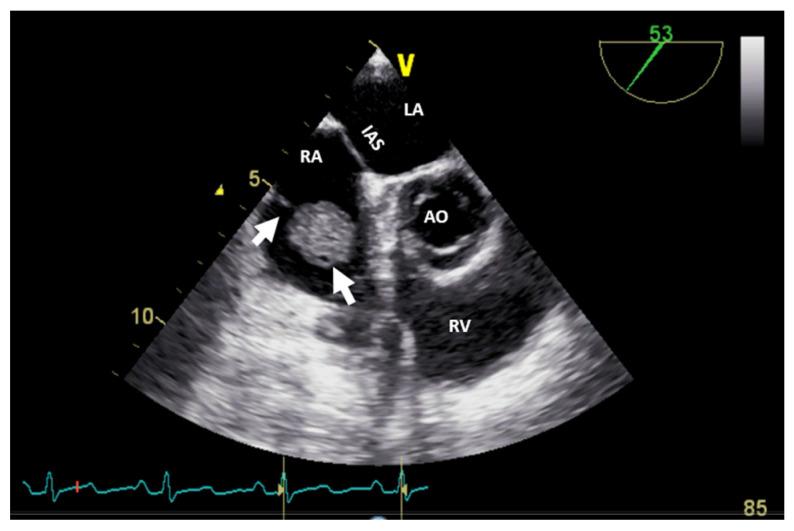

A right heart tumor can be identified by transthoracic echocardiography during a routine examination or due to cardiac symptoms. The first step is the assessment by echocardiography, with its multiple techniques, and the obtained information must be judged in a clinical and biological context. The second step comprises one, sometimes even two, of the more complex modality imaging methods. The choice is driven not only by the advantages of each imaging technique but also by local expertise or the preferred imaging modality in the center. This step is followed by staging, follow-up, and/or imaging-guided excision or biopsy, which is performed in selected cases in order to obtain anatomopathological confirmation. In the presence of features suggestive of malignancy or causing hemodynamic impairment, a transvenous biopsy is essential before the more complex imaging modalities (which are still relevant in the staging process). Using a structured imaging approach, it is possible to reach an appropriate diagnosis without a biopsy. Frequently, these imaging techniques have a complementary role, so an integrated imaging approach is recommended. This proposed algorithm for appropriate diagnosis of right heart tumors could serve as a practical guide for clinicians (not only imaging specialists).

右心肿瘤可在常规检查期间或因心脏症状通过经胸超声心动图得以识别。第一步是采用多种技术进行超声心动图评估,且必须在临床和生物学背景下对所获信息进行判断。第二步包括一种,有时甚至是两种更为复杂的影像学检查方法。其选择不仅取决于每种成像技术的优势,还取决于当地的专业水平或该中心首选的成像方式。此步骤之后是分期、随访和/或成像引导下的切除或活检,在特定病例中进行这些操作以获得解剖病理学确认。若存在提示恶性或导致血流动力学损害的特征,则在采用更复杂的成像方式(在分期过程中仍具有相关性)之前,经静脉活检至关重要。采用结构化成像方法,无需活检也有可能做出恰当诊断。这些成像技术常常具有互补作用,因此建议采用综合成像方法。这种针对右心肿瘤恰当诊断的提议算法可为临床医生(不仅是影像专家)提供实用指南。